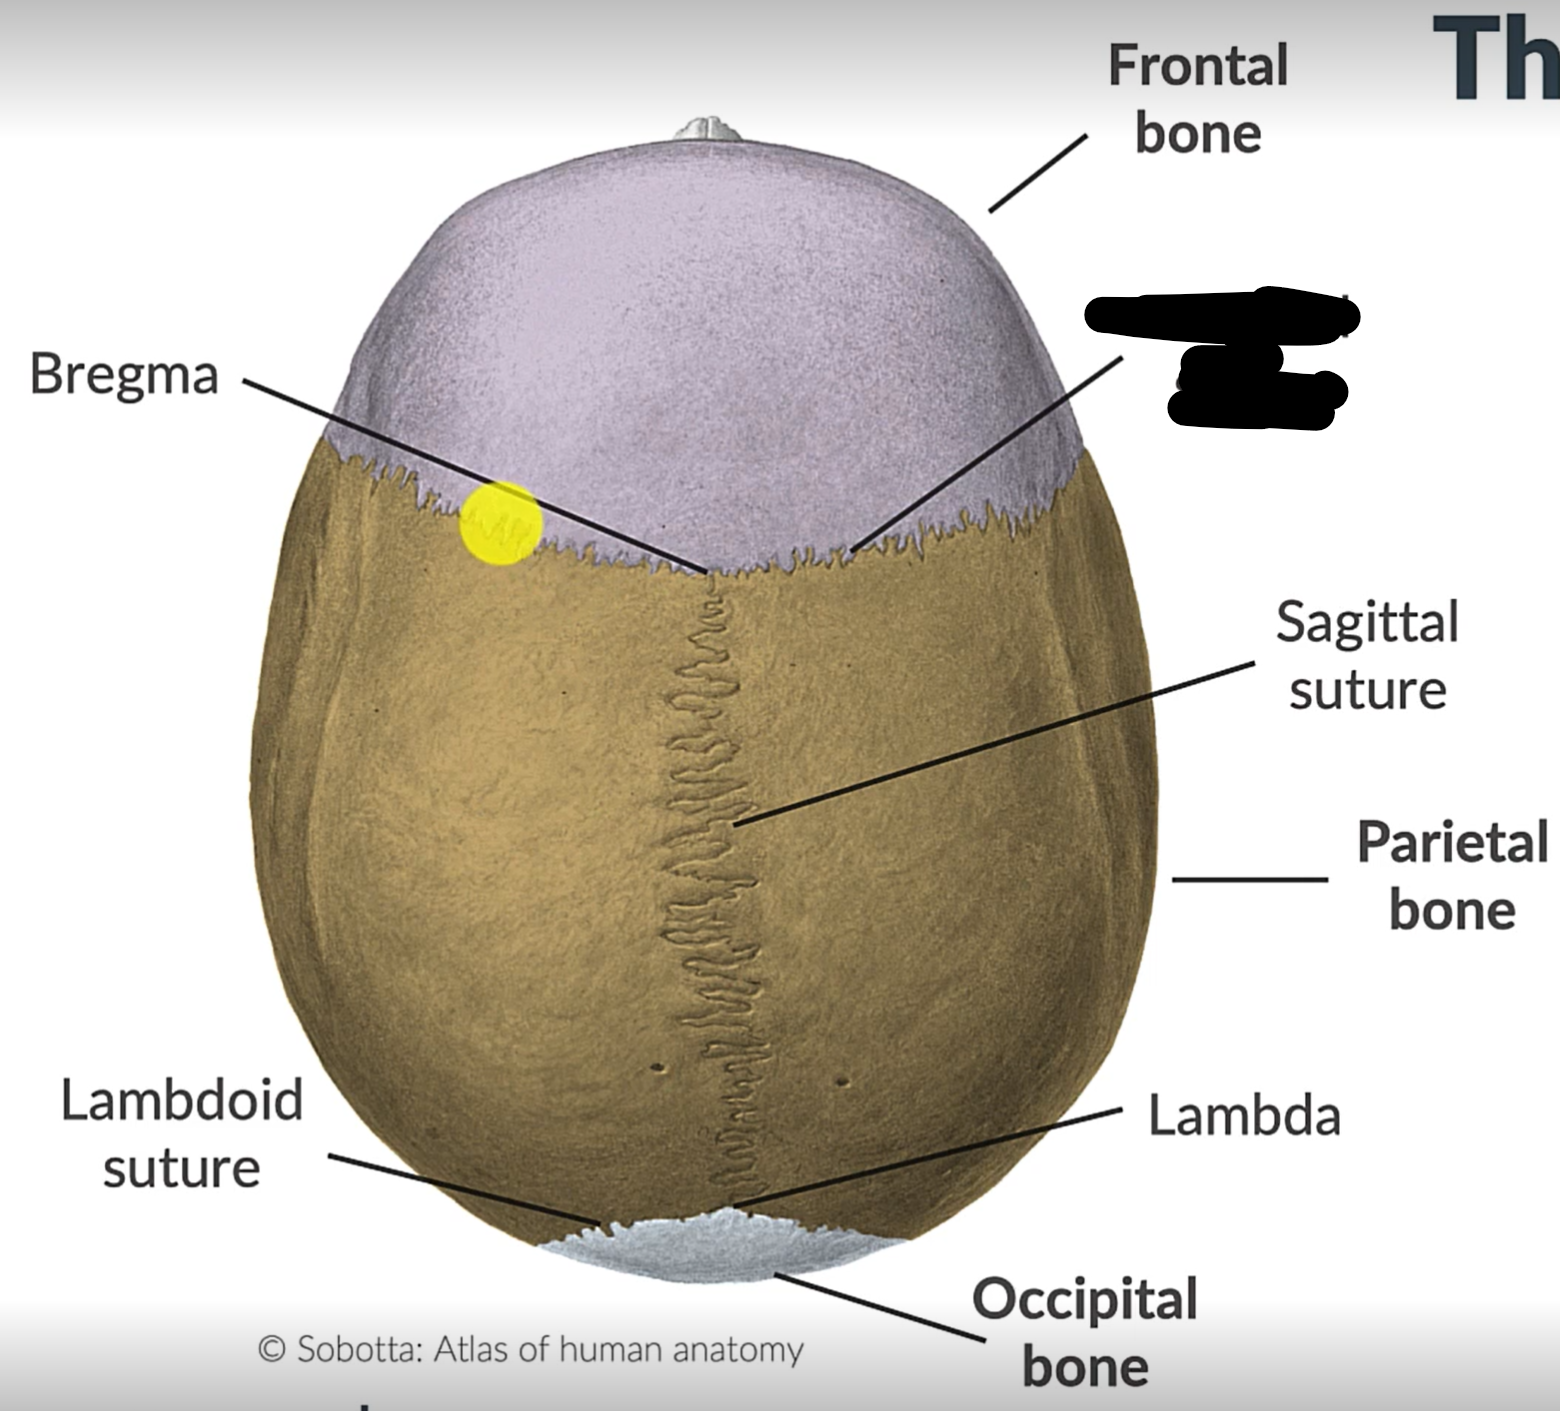

What are the 4 cranial sutures and what do they separate?

Lambdoid - separates occipital from parietal and temporal

Sagittal - extends between parietal bones

Coronal - divides frontal and parietal bones

Squamous - either side of cranium, separates temporal and parietal bones

Sagittal suture

Lambdoid suture

Occipital bone

What is the point where the frontal and parietal bones meet?

Bregma

Lambda